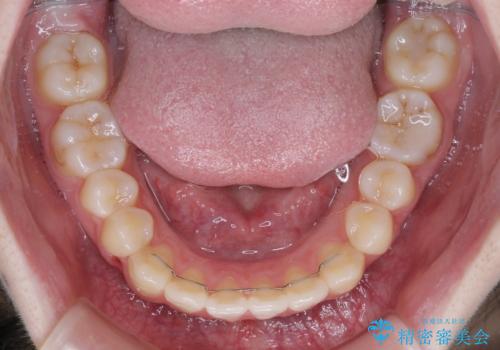

カリエールディスタライザーを併用したことで、左側臼歯の咬み合わせを確実に改善させることができました。

- 前歯の叢生と上顎左右の八重歯を気にして来院された患者様です。

奥歯の咬み合わせを見ると、左側は上顎が下顎に対して相対的に前方にあり、上下の前歯が接触していない状態でした。

咬み合わせを改善するためには、左側上顎臼歯を後方に移動させた咬み合わせにする必要があります。

インビザライン単体で改善することも可能性もありますが、インビザライン単体で達成する可能性が低いと考えられたため、カリエール・ディスタライザーという補助装置を併用して、より確実性を上げることとしました。

奥歯の咬み合わせを改善しながら、並行してインビザラインで歯列を整えることとしました。